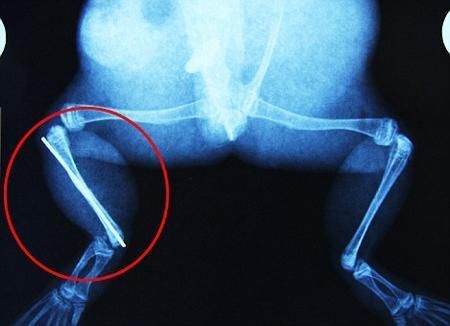

環(huán)球網(wǎng)4月2日報道 據(jù)《每日郵報》報道,上個月,南非大牛蛙布魯萊的右小腿被鄰居家的一只狗咬到,導致粉碎性骨折,現(xiàn)在經(jīng)過2個小時的手術(shù),它的斷腿已經(jīng)被接上,它也因此成為有史以來第一只通過外科手術(shù)用鋼針接上斷腿的青蛙。

布魯萊的主人,居住在南非約翰內(nèi)斯堡附近的62歲的安妮·米恩斯說:“我對這只青蛙如此關(guān)心,人們一定認為我瘋了,但是我無法眼睜睜看著它那么痛苦。青蛙因其靈活的腿腳而著稱,一想到布魯萊的腿里要留下一個薄金屬片,我就感到心痛。然而我知道,如果不進行手術(shù),布魯萊以后就沒辦法動彈了。因此我匆匆趕到獸醫(yī)那里,央求他給這只可憐的青蛙動手術(shù)。這位獸醫(yī)整天救助小貓小狗,他很難理解為什么我這么擔心一只青蛙,但是最終他還是答應(yīng)了給布魯萊做手術(shù)。手術(shù)后是幾個小時的焦急等待,我們希望它能快快蘇醒過來。不過現(xiàn)在它的傷口已經(jīng)愈合,又能在花園里跳來跳去了。X光照射顯示,它會恢復的跟以前一樣。”

野生生物專家安妮經(jīng)常為學校寫教材,她認為這是人類第一次通過手術(shù)給一只青蛙接斷腿。在手術(shù)開始階段,獸醫(yī)把少量給狗用的麻醉藥注入到這只青蛙體內(nèi),讓它失去知覺。然后他在布魯萊的斷腿上切開一個小口,把一根小鋼針植入腿里。最后獸醫(yī)給它縫了9針,把切口縫合在一起。僅僅幾周后,布魯萊就能在安妮家附近活動了。這只青蛙大約已有25歲,主要以嚙齒動物、蛇和其他青蛙為食。布魯萊所屬的牛蛙種群正在不斷減小,目前只能在非洲南部的濕地里才能看到這種青蛙。